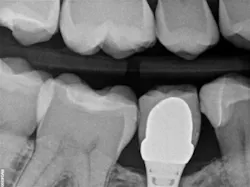

Recently, I changed my protocol for doing Class II dental restorations. I have started using indirect restorations more often. Depending on the size of the restoration, I now use indirect composites, inlays, onlays, and occasionally full-coverage crowns. Using indirect restorations allows one to control the emergence profile of the restoration and also ensures tight proximal and broad interproximal contacts. See Figures 3 through 6.

present at DL line angle not seen on radiograph.

food debris in the contact area.

embrasure space. Distal of No. 28 was restored as well;

not seen in this radiograph.